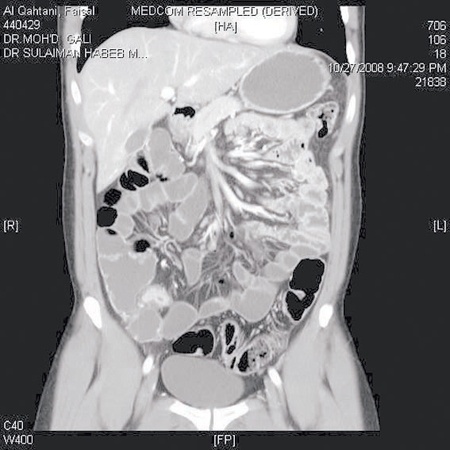

الأشعة المقطعية للقلب هي عبارة عن مجموعة شرائح رفيعة تصور بواسطة الأشعة السينية أو أشعة إكس، حيث يدور الجهاز في ثوان حول جسم المريض لالتقاط الصور ويقوم الحاسوب بتجميع الشرائح وعرضها على الشاشة في شكل صور مقطعية ثلاثية ورباعية الأبعاد، كما تظهر الأشعة أجزاء القلب مع الشرايين التاجية وباقي الأوعية الدموية بعد حقن صبغة من مادة اليود.

تصوير الجسم كله بسهولة تامة

كما أن هذا الجهاز قادر على التنويع في الفحوص، حيث بالإمكان فحص جميع أجزاء الجسم دون استثناء، فالفحوص التي كان يصعب عملها بالأجهزة القديمة أصبحت سهلة جداً وفي متناول اليد وتشمل فحوص الدماغ، الرقبة، البطن، الحوض، الكبد، القنوات المرارية ثم الفحوص الملونة لشرايين الدماغ، شرايين الرقبة التي تغذي الدماغ وشرايين الصدر والبطن والكلى ثم شرايين الأرجل, وخاصة عند مرضى السكري, إذ يتم تشخيص تضيق أو انسداد تلك الشرايين ليتم العلاج بأسرع وقت وهذا يغني تماماً عن القسطرة التشخيصية وما لها من مضاعفات.

تستخدم هذه التقنية في تصوير الأمعاء الدقيقة بجهاز التصوير الطبقي ولها فوائد عديدة مثل فحص جدار الأمعاء من الداخل وكذلك من الخارج وفحص أجزاء الأمعاء الدقيقة بصورة أكثر وضوحاً وخاصة المركبة أو الملتوية على بعضها. كما تتيح هذه التقنية للطبيب فحص الأوعية الدموية وكذلك الدهون المحيطة. ويجب ألا ننسى أنه بهذه الطريقة يتم أيضاً فحص الأعضاء الداخلية الأخرى من: كبد، طحال، بنكرياس، كلى، وأمعاء غليظة.

لقد أثبت تصوير الأمعاء الدقيقة بجهاز الطبقي أنه أكثر دقة في معرفة التغيرات السطحية في الجدار الداخلي للأمعاء مثل الزيادة في سمك الجدار والثقوب في الأمعاء وكذلك وجود الدمامل في حالات الالتهابات المعوية مثل مرض كرونز وكذلك عند احتمال وجود انسداد معوي وفي هذه الحالة نستطيع معرفة ماهية المسبب لذلك الانسداد، وكذلك تتم معرفة الالتصاقات الناتجة عن الالتهابات التي قد تسبب انسدادا معوياً.